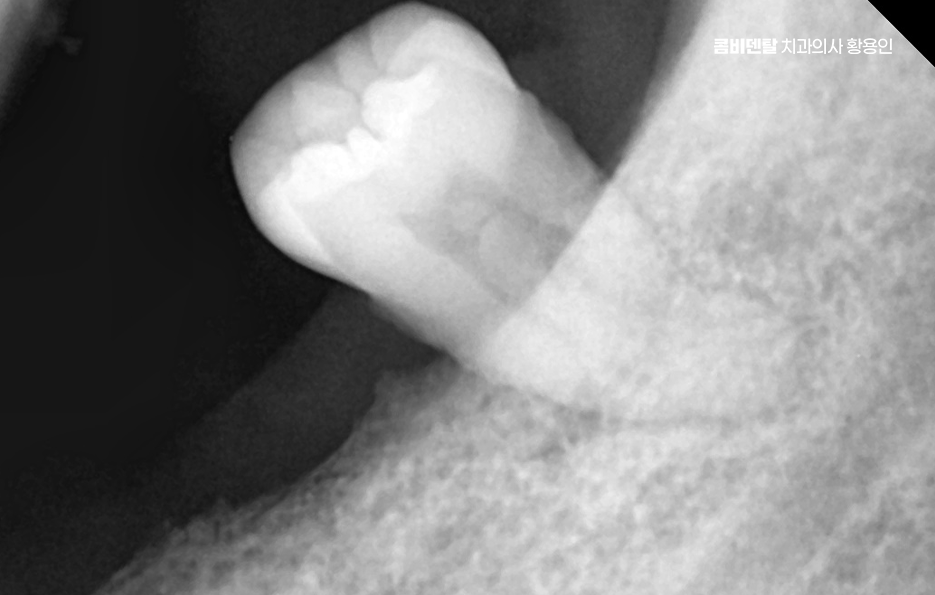

어금니 발치후 임플란트 안하면 먼저 생기는 문제는 치아 이동 현상으로 사람의 치아는 서로 의지하면서 균형을 맞추고 있는데, 어금니 하나가 빠지게 되면 그 자리를 메꾸기 위해 옆 치아들이 점점 쓰러지듯이 기울어지며 또 위아래 맞물리던 치아는 상대 치아가 사라지면 아래로 내려오거나 위로 솟구치면서 위치가 틀어질 수 있어요

결국 전체 치열이 뒤틀리고 교합이 망가지게 되는 것인데 이건 단순한 배열 문제가 아니라, 턱관절까지 영향을 줄 수 있는 변화로 이어지는 거예요.

그리고 사실 골 흡수의 문제가 무척이나 큰데 즉 잇몸뼈가 점점 사라지는 현상으로 치아가 뿌리로 잇몸뼈에 자극을 주고 있어야 뼈가 유지되는데, 치아가 빠진 상태로 계속 방치되면 그 부위 뼈는 서서히 꺼지듯이 흡수되기 시작하는 거예요.

이게 심해지면 나중에 임플란트를 하고 싶어도 뼈가 부족해서 뼈이식까지 같이 해야 하고, 수술 범위도 커지는 것이며 임플란트를 하지 않고 방치한 시간이 길수록 치료가 까다로워지고, 비용도 더 많이 들어가는 문제가 발생될 수 있었어요